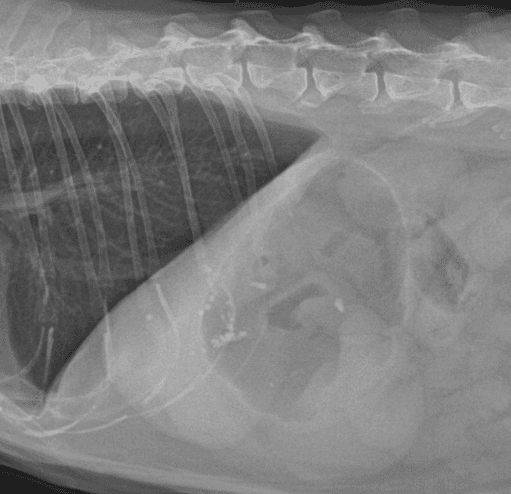

동탄 1 신도시 최초 Aquilion CX/128 slice CT를 동물병원에 도입하였습니다. 최고 사양 CT 모델 Aquilion CX/128 slice를 활용하여 0.5 mm의 얇은 128개의 단면 영상을 신속히 획득 할 수 있어 마취 시간을 단축시킬 수 있습니다. 또한, 128 슬라이스의 고화질의 CT 영상을 통해 영상 왜곡을 최소화하고 X-ray에서는 확인하기 힘든 5 mm 이하의 미세 병변도 확인이 가능하여 정확한 진단을 할 수 있습니다. 심화 진단이 필요한 경우, 조영제 인젝터를 통한 동맥기 촬영으로 종양 유래 확인, 간 질환 진단, 심혈관계 진단이 용이합니다. 저희 동탄시티동물의료센터에서는 본원 환자뿐 아니라 1차 동물 병원과의 CT 촬영 의뢰 시스템을 통해서 원활한 협진이 가능하도록 최선을 다하고 있습니다.

0164 채널 CT 촬영을 통해서 신속하게 고화질 영상을 얻어, 종양 유래 확인 및 전이 평가, 간문맥단락증(PSS), 선천적 뼈 기형과 같은 심화된 진단을 할 수 있습니다.

64채널 검출기 시스템 128

슬라이스 이미징 능력

고속 스캔 및 높은 해상도 제공

저선량 기술 적용으로 환자 방사선 노출 감소

흉복부, 골격계 전반의 선명하고 우수한 영상을 저선량으로 촬영이 가능